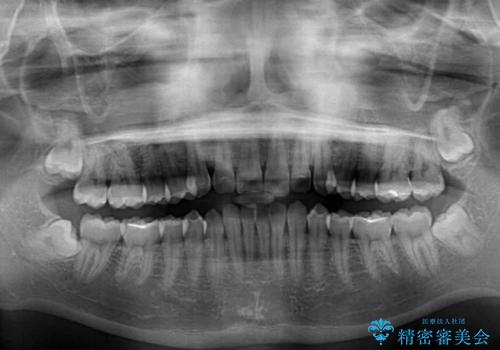

- 上下前歯の重なりを気にして来院された患者様です。

安価なインビザラインパッケージを用いての治療を希望されており、デコボコの程度が中等度であったため、インビザライン・モデレートを用いて矯正治療を行うこととしました。

インビザライン・モデレートは、製作できるアライナーの枚数に制限があるため、移動可能な量に限りがあるものの、インビザライン・ライトよりも枚数が多いため、幅広い症例に対応可能です。